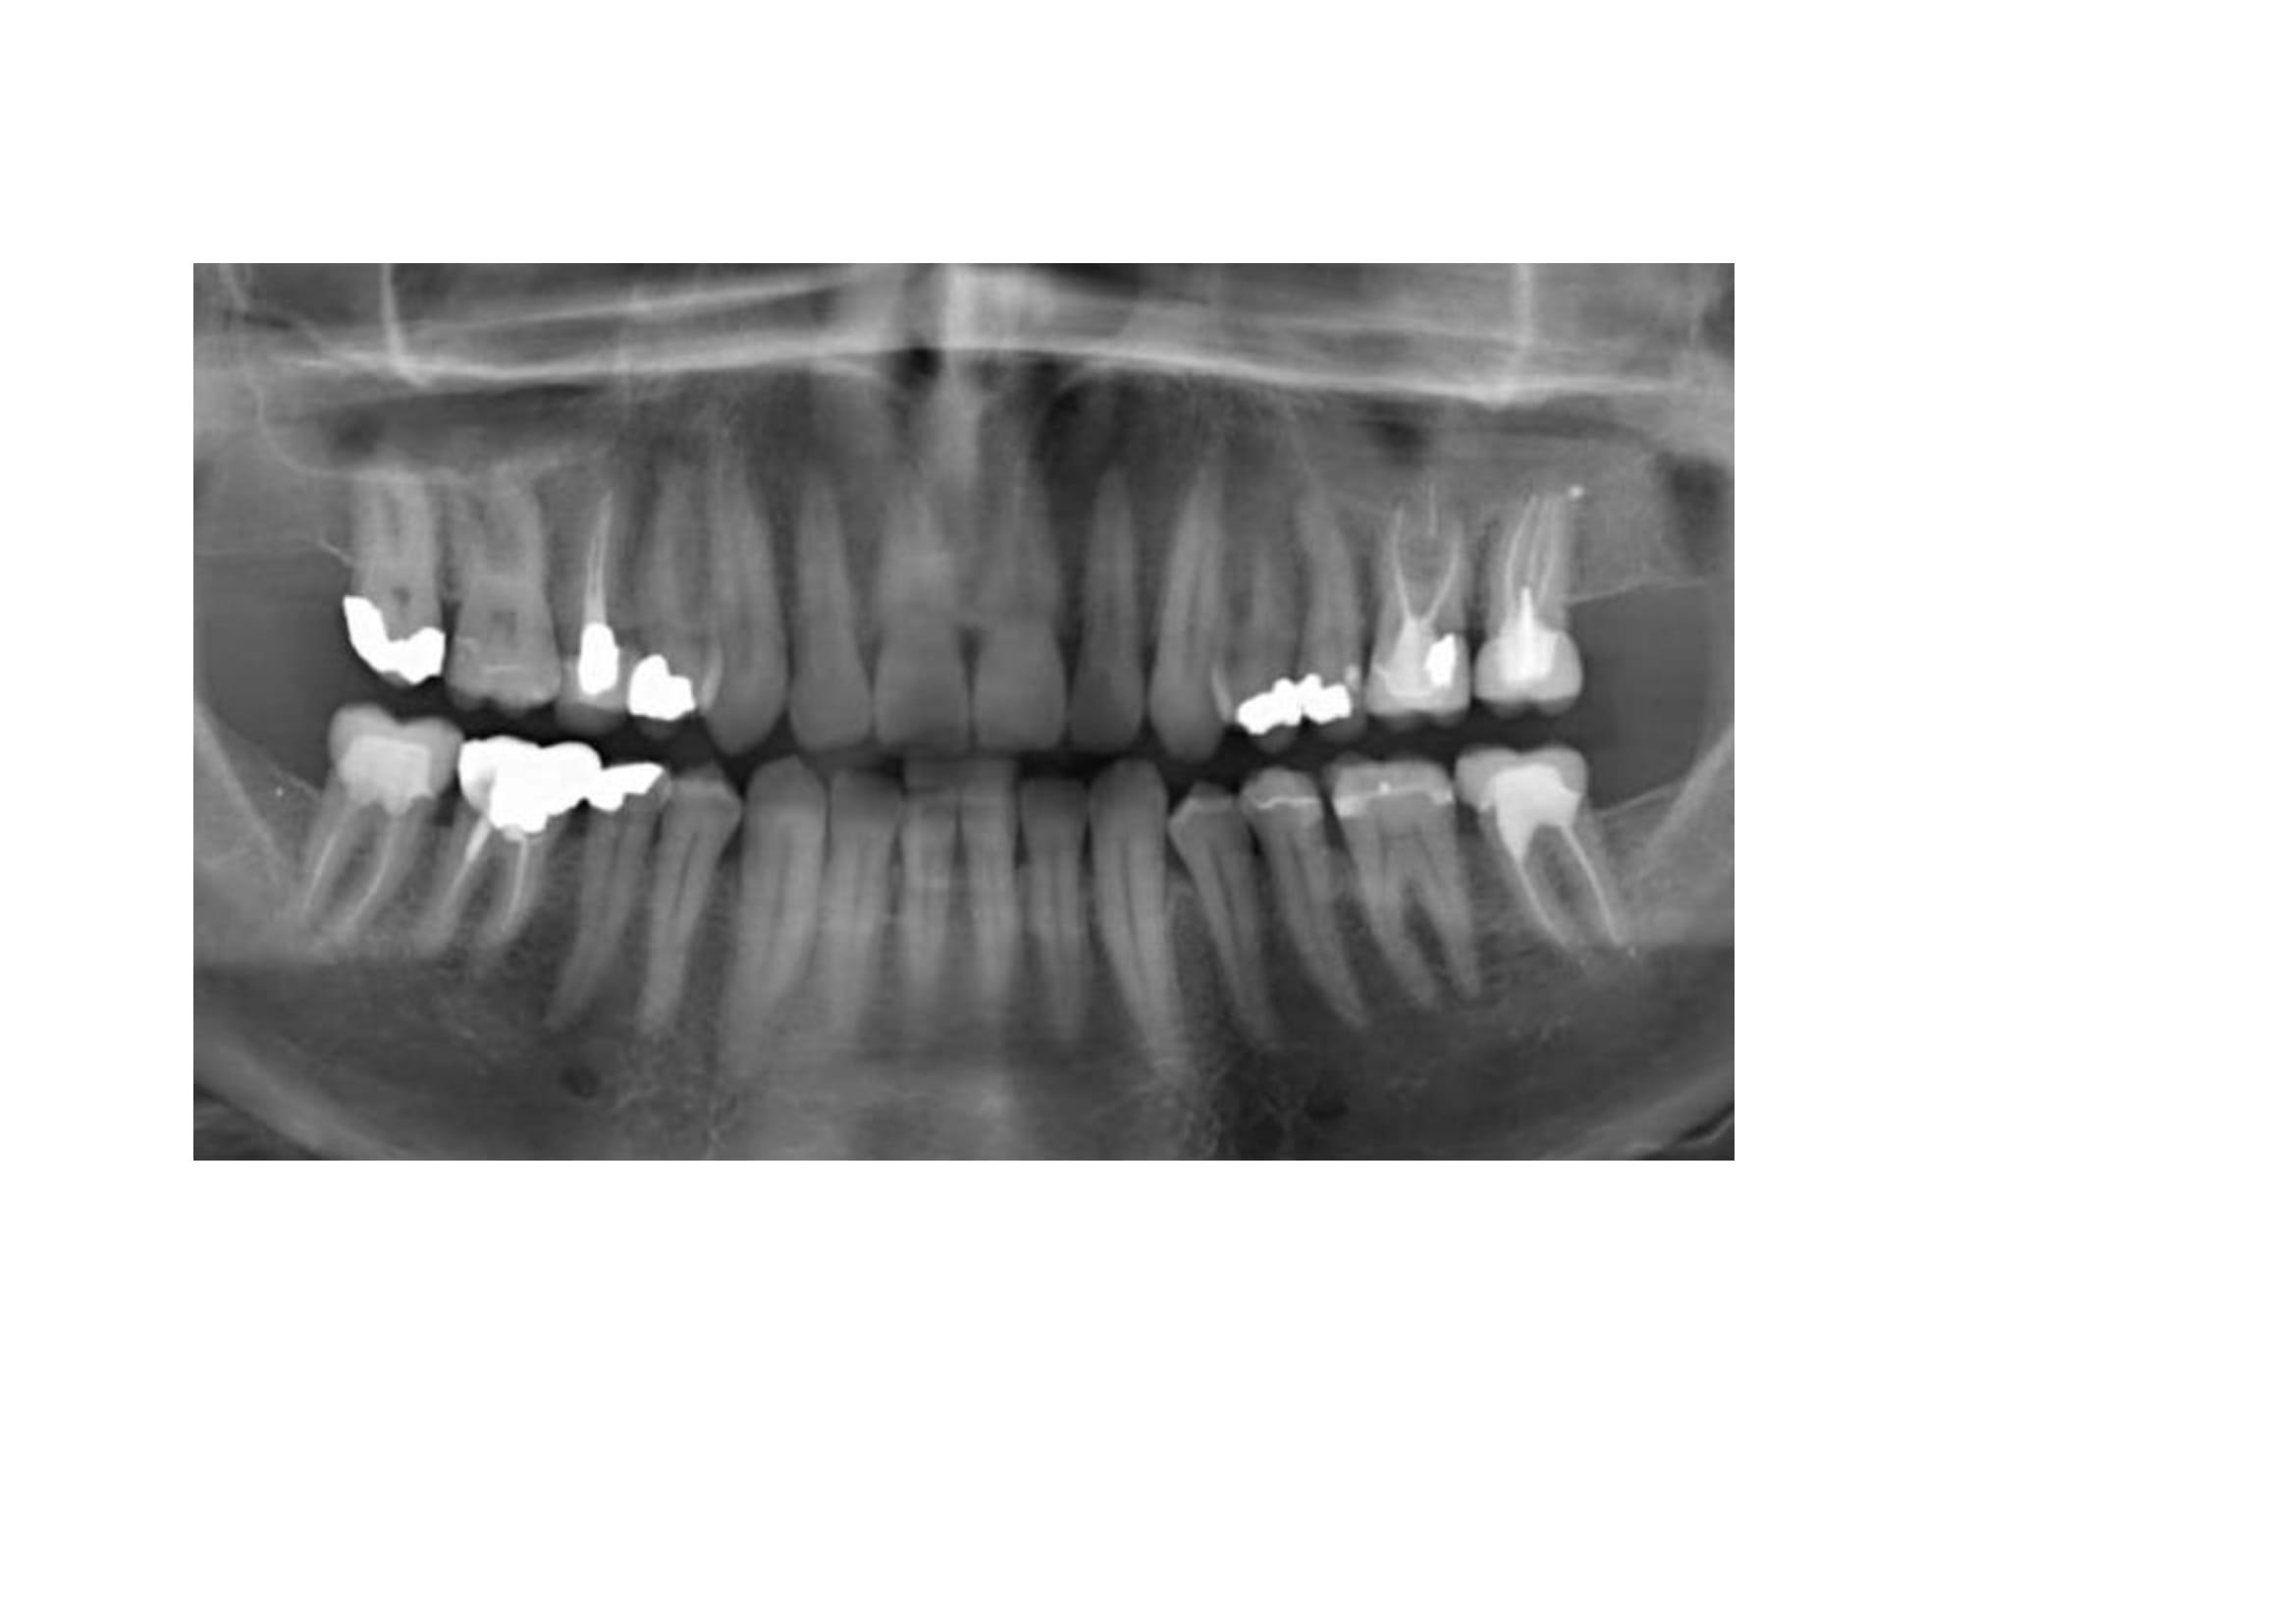

A toutes fins utiles, pour les nouveaux lecteurs, je reposte mes radios.

en ajoutant la 42 également.

Et pourquoi ne pas retraiter la 37 dans un premier temps qui présente une lésion sur la racine mésiale avec un traitement court et une lésion sur la racine distale avec un traitement adéquat?

Bonjour PtnBZ..effectivement l'endo ne va pas jusqu'à l'apex..mais...comme on ne voit pas de tache sombre ..on peut supposer que pas d'infection ?

Sur la radiographie ce n'est pas clair, peut être éliminer les causes les plus probables et les plus simples à régler avant de passer aux moins probables. Ce serait idéal de refaire un examen complet.

1/ une lésion apicale peut ne pas se voir sur une radio 2D c'est si dur à comprendre pour toi ?

2/ 1 seul canal a été traité sur cette 37 alors que c'est rare d'avoir que 2 canaux

3/ on peut avoir des douleurs d'origine endo sans forcément avoir de lésion apicale, hé oui

4/ la 26 n'est pas claire

Le traitement en mésial de 37 n'est pas bon çà se voit tout de suite, peut-être un canal a été oublié, en tout cas un manque d'étanchéité.

Dans un cas comme çà, si cliniquement je vois que la dent est sensible (en écartant la possibilité d'une surocc) et même si le CBCT ne montre rien, je redémonte 37 et refait l'endo, avec le risque effectivement que çà ne change rien mais au moins le traitement sera correct et on peut écarter cette hypothèse à 100%.

C'est marrant que la 37 vous interpelle, alors que la 35 (meme la 45!) est beaucoup plus louche, avec un compo juxta pulpaire (mauvais mariage) , et certainement une mortification lente a bas bruit, le truc bien vicelard au diagnostic differentiel difficile.